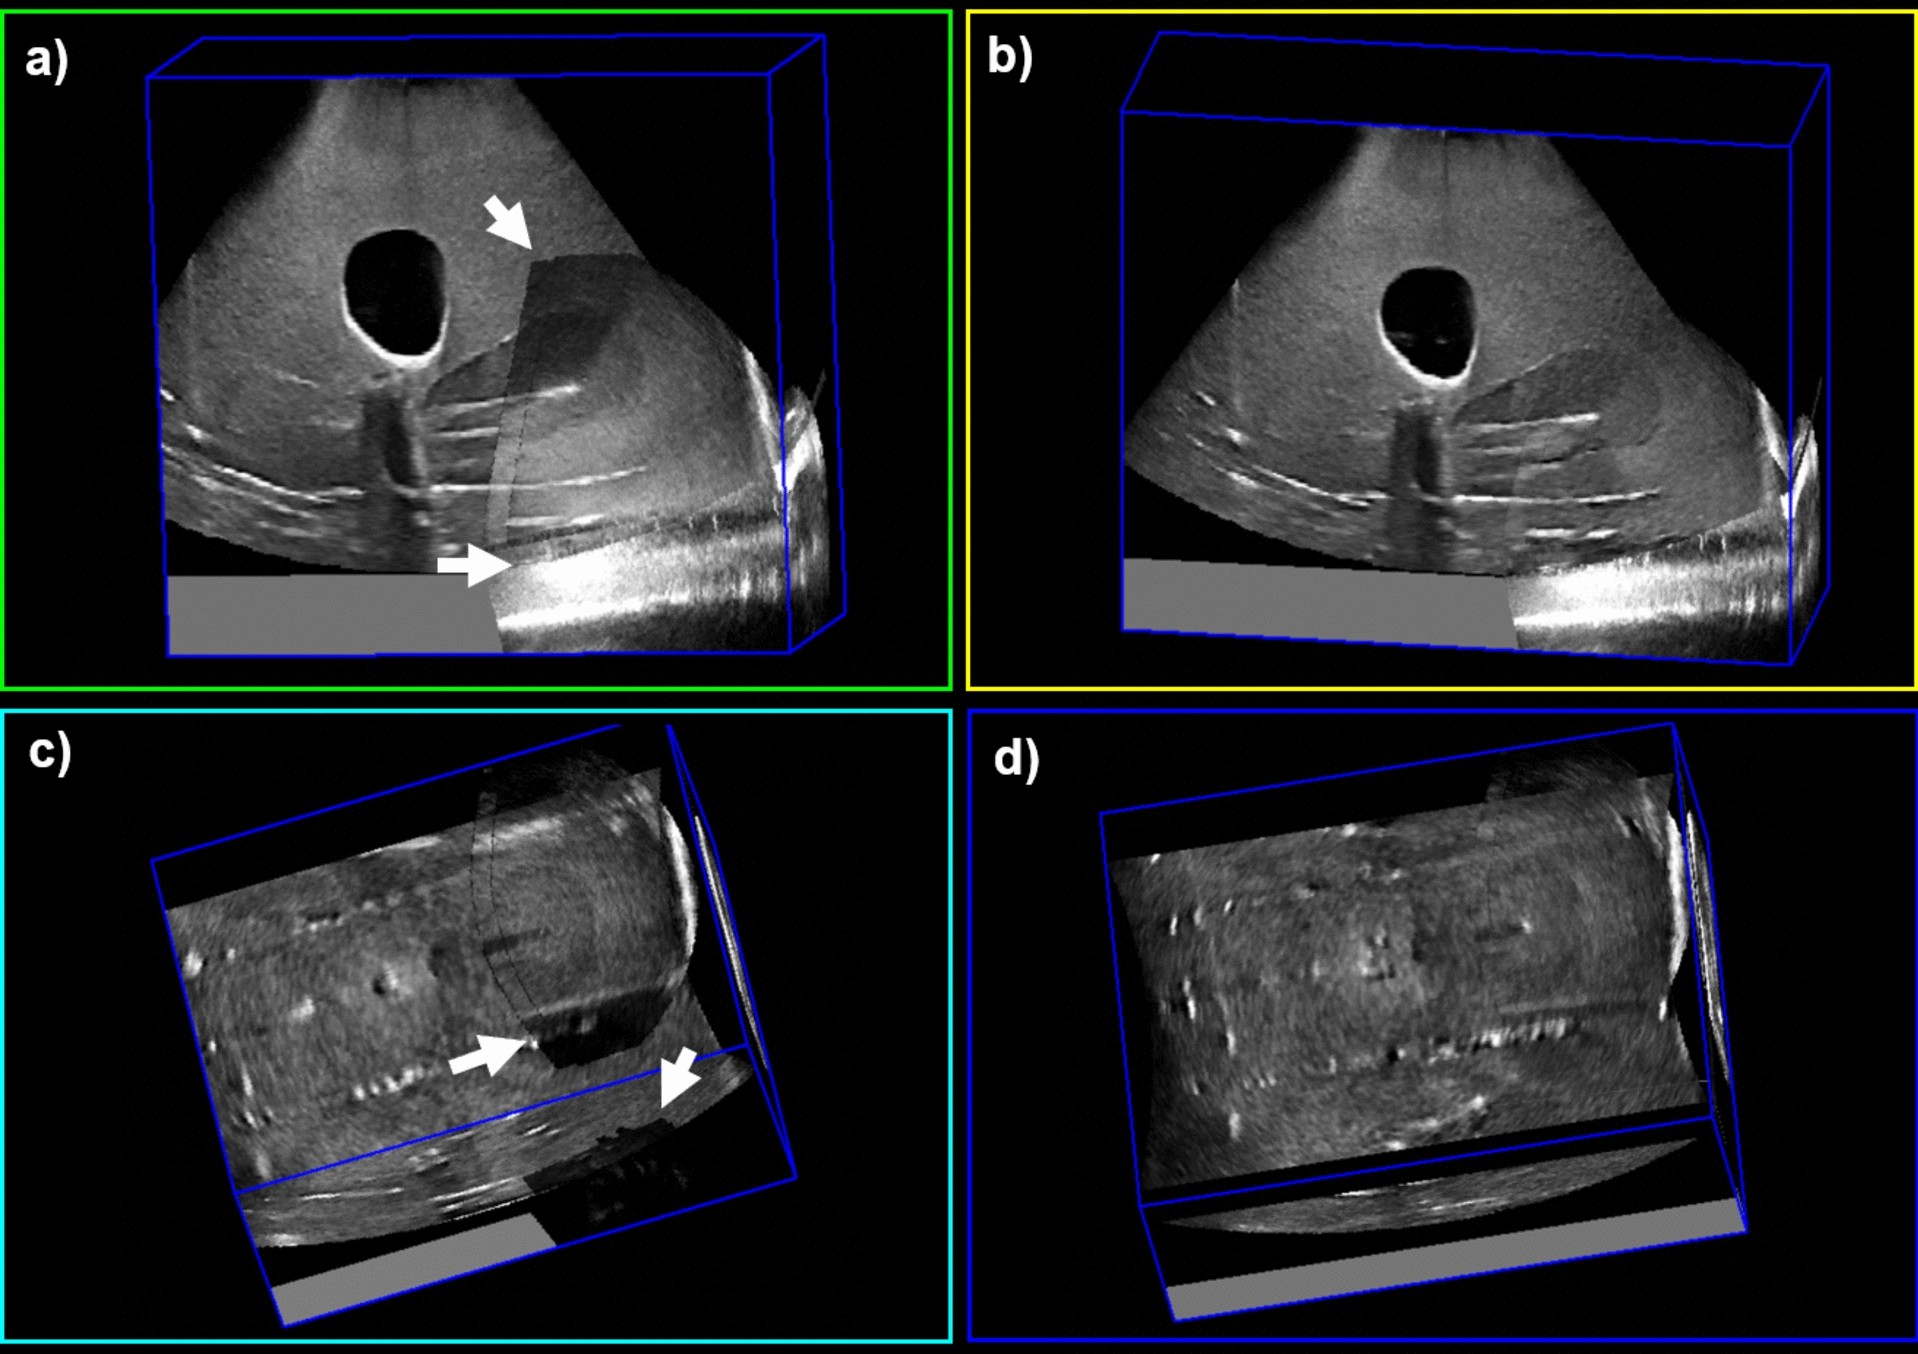

Figure 3

Fused 3D US images of a Vienna ring-and-tandem phantom. (a) and (c) depict sagittal and coronal views of images fused using an averaging function, respectively. Arrows indicate regions of shadowing or reflection artifacts that are present. (b) and (d) depict sagittal and coronal views of images fused using our updated weighting function. Note the lack of image artifacts in regions corresponding to the arrows in the left figure panels.